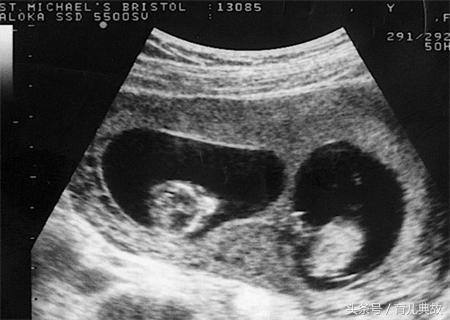

直到怀孕三个月去建卡,第一次产检,有孩子后小姚和老公只祈求宝宝健康就好却没想到宝宝却给了这么大的一个惊喜!医生在做B超的时候说有两个宝宝,胎心胎芽都有。

单胎变双胎的惊喜真的太不可思议了,何其幸运能一次迎来两个宝宝。为了更好的照顾小姚还特意叫小姚婆婆过来,这样老公方能安心的去上班赚钱给孩子买奶粉钱!

医生表示,若早期孕囊B超单上出现"宝宝偏大一周/两周"的字样的时候是有可能从单胎变双胎的,在现实生活中也有过不少案例。对于如此好孕,你也有吗?